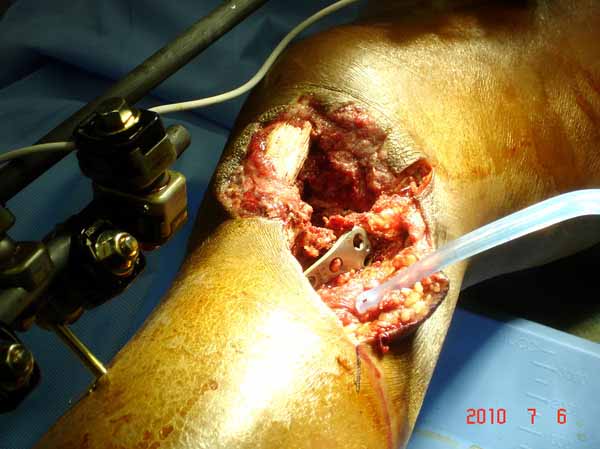

----------- следущая часть -----------

Вложение не в текстовом формате было извлечено…

Имя     : 24 gsw plate.jpg

Тип     : image/jpg

Размер  : 55086 байтов

Описание: отсутствует

Url     : http://weborto.net:8080/pipermail/ortho/attachments/20110617/500d7d65/attachment-0009.jpg